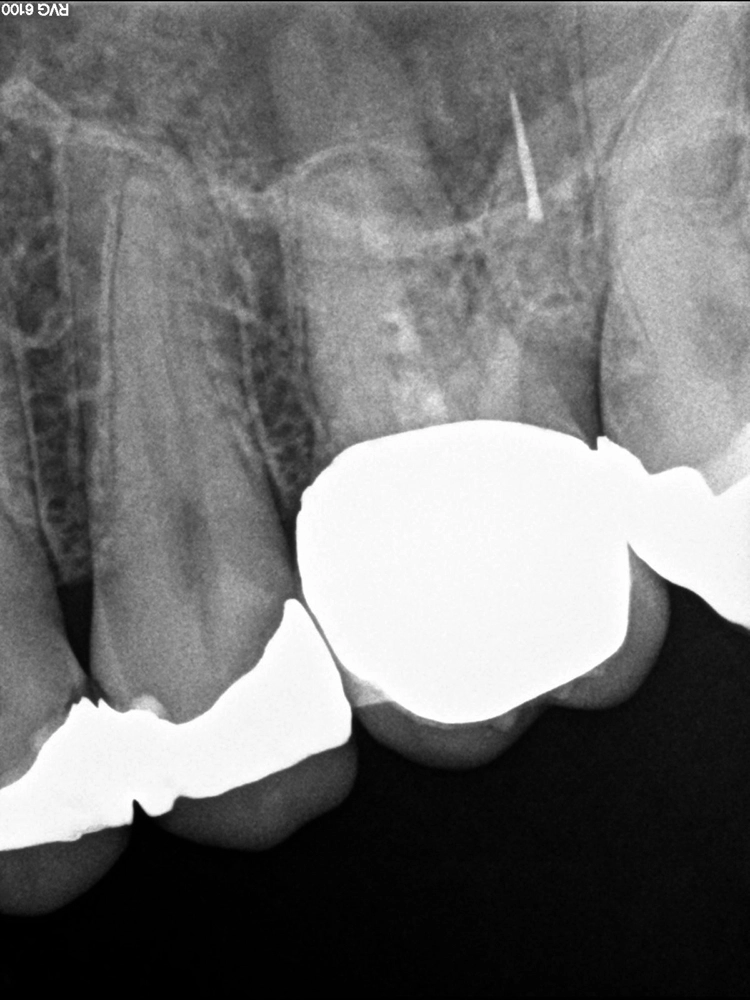

Die Lage des Fragmentes in Bezug zur Krümmung des Wurzelkanals wirkt sich direkt auf die Entfernbarkeit aus: Die Erfolgsaussicht ist hoch, wenn das Fragment koronal der Krümmung lokalisiert ist, moderat, wenn das Fragment in der Krümmung liegt und als gering bei apikaler Lage zu bewerten [5]. Die Erfolgsrate für die Entfernung fakturierter Instrumente sinkt von 83 auf 43%, wenn der Krümmungswinkel der Wurzelkanalkrümmung 20º übersteigt. Darüber hinaus ist die Entfernung erleichtert, wenn der Krümmungsradius größer als 4 mm ist [3].

Die diagnostische Grundlage für eine sichere Lagebestimmung und Abschätzung der Zugänglichkeit des zu entfernenden Instrumentenfragmentes stellt eine zweidimensionale intraorale Röntgenaufnahme (Zahnfilm) dar, die bei Bedarf durch eine 2. Aufnahme aus einer alternativen Projektionsrichtung ergänzt werden kann. Im Ausnahmefall ist eine dreidimensionale Darstellung (DVT) hilfreich.

Im 1. Behandlungsschritt erfolgt die Korrektur der vorliegenden primären Zugangskavität (Zugang zur Pulpakammer) mit dem Ziel, einen geradlinigen Zugang zum Wurzelkanallumen sicherzustellen. Dieser Behandlungsschritt ist die Voraussetzung dafür, dass auch im mittleren bzw. apikalen Wurzeldrittel verbliebene Fragmente visuell dargestellt werden können. Im 2. Schritt wird der Zugang zur koronalen Bruchfläche des Fragmentes hergestellt.